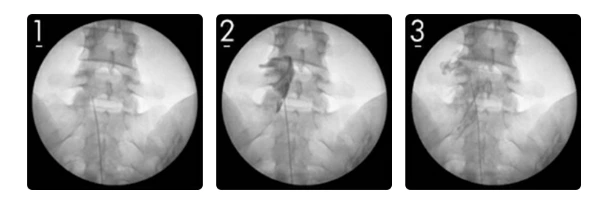

경막외신경성형술이라고 불리는 치료로 비수술적인 치료방법 중에서도 효과적이며 부담이 없는 치료로 많이 사용되고 있습니다. 가느다란 카테터(약물 주입이 가능한 관)를 이용해 척추신경 주위에 자라는 불필요한 조직을 기계적, 화학적으로 치료하는 시술이지요. 방사능 영상장치(C-arm)로 통증 부위를 찾아내기 때문에 정교하고 세밀한 통증 부위를 확인해 치료가 가능합니다.

허리신경성형술.PNG

C-ARM이라는 방사선 영상장치로 통증 부위를 찾아내기 때문에 육안으로 확인하는 것과 견주어 훨씬 정교하고 세밀한 부분까지 확인해 치료가 가능하다는 장점이 있습니다. 통증을 일으키는 원인에 대한 직접적인 치료로 통증 개선 효과를 내는 것이지요.

이런 과정에서 허리 신경성형술이 결정되었다면 우선 국소마취 후, 꼬리뼈를 통해 척추 내부와 연결되는 통로로 카테터가 지나갈 통로가 될 주사기를 주입합니다.

다음은 실시간 영상을 보며 원격조정이 가능한 특수 카테터를 삽입하고 통증 및 염증을 유발시키는 병변을 정확히 찾아내 기계적으로 병변과 주변 조직 간의 유착된 부분을 박리시키고 치료제를 주입해 화학적으로 유착된 신경을 풀어줍니다.

이 모든 과정은 실시간으로 화면을 통해 확인하며 진행되기 때문에 정확한 치료가 가능하지요.